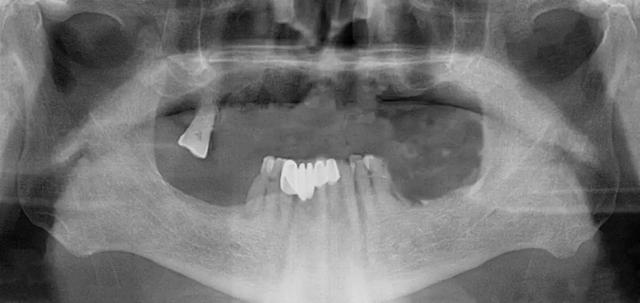

家住安丘的郎先生,因上牙床僅剩一顆牙齒,吃飯很受影響。在了解到濰坊市中醫(yī)院口腔科種植全口牙當(dāng)天可以接著戴牙吃飯,慕名來(lái)找李德仁主任尋求幫助。

口腔科李德仁主任為老人仔細(xì)檢查了口腔情況,由于缺牙時(shí)間太久,牙床骨量極少,正常的種植修復(fù)需要植骨,手術(shù)創(chuàng)傷大而且半年后才能鑲牙吃飯。建議他進(jìn)行數(shù)字化導(dǎo)板種植,可以不用植骨而且當(dāng)天就能戴牙吃飯,手術(shù)簡(jiǎn)單,創(chuàng)傷小。老人和孩子很信任的接受了李主任的種植方案:上牙床種植5顆,下牙床種植4顆,當(dāng)天戴牙吃飯。